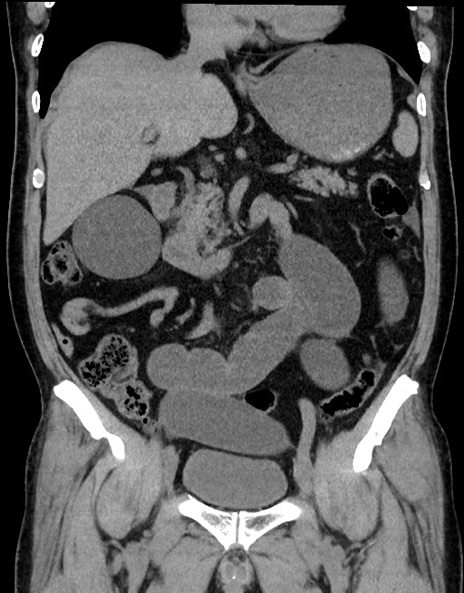

症例15(冠状断像)

【症例】70歳代男性

【主訴】腹痛

【現病歴】今朝から腹痛あり。全体的に痛い。特に左上の方。排ガスが今日はない。冷や汗が出る。

【既往歴】直腸癌術後

【身体所見】左側腹部〜上腹部に圧痛あり。腹膜刺激症状明らかなではない。軽度反跳痛。左下腹部に術後瘢痕あり。

【データ】WBC 7700、CRP 0.02